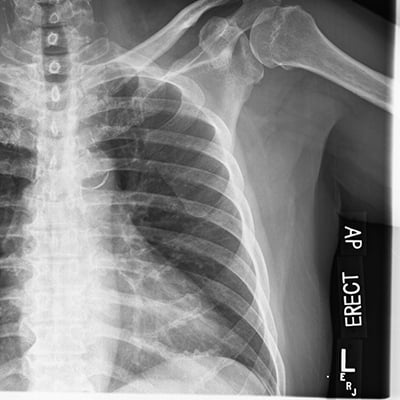

This module will help you achieve optimal images of the chest and abdomen, including AP and lateral decubitus chest examinations, and supine, upright, and decubitus abdomen examinations are also covered. Patient positioning, technical settings, and patient instructions are discussed. Descriptions and images of the expected anatomical structures are included, as well as image evaluation criteria.